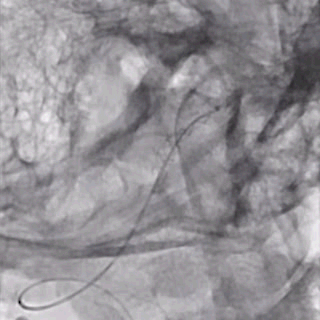

支架及支架微导管到位。

支架头端打开。

支架远端打开造影。

等张释放,支架中段打开至50%释放标记点。

支架中段打开造影。

支架近端打开,完全释放。

支架完全释放造影。

术后即刻造影。